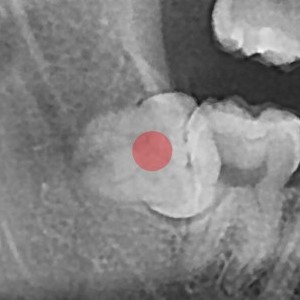

智齿拔除 完全埋伏智齿